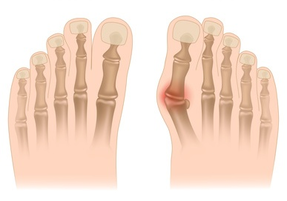

Hallux valgus (deformed thumb) is a condition in which the thumb of the foot is turned outwards, often with the formation of a painful squat. The most common causes are tight footwear, genetic predisposition and neuromuscular disorders. It can cause pain, swelling, walking problems and deformation of other fingers.